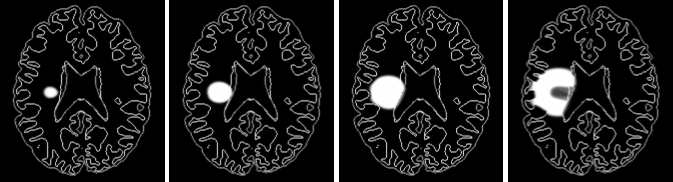

Gliome - croissance avec angiogenèse